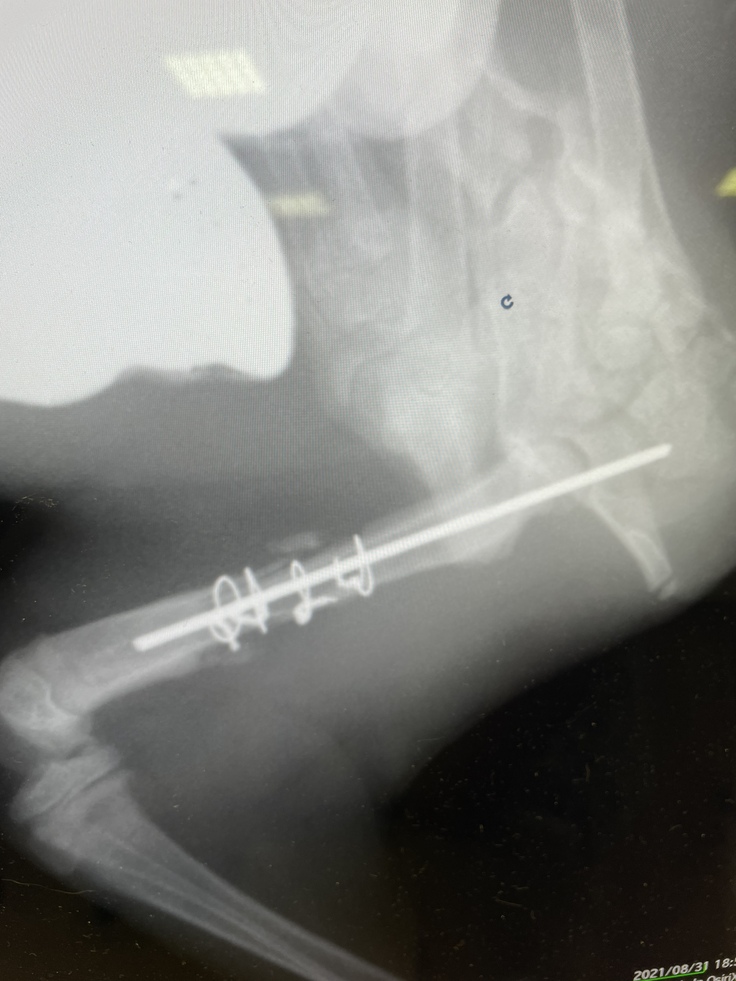

⑤再手術(9月16日)

ピンが皮膚を突き破りそうなため、摘出を行いました。幸い抜き取る事が出来たので、切開も小さい範囲で済みました。ワイヤーは残したままです。

皮膚はまだ盛り上がっていて、蓮も気になるみたいで舐めたり噛んだりしています。

骨はまだ散らばっていますので、左後脚に力を入れるのが難しく、走ったり飛んだり跳ねたりは出来ず、まだぎこちない歩き方です。

↓[摘出したピン]